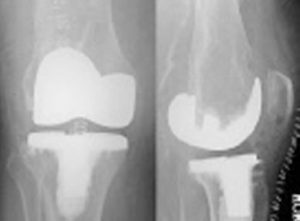

TOTAL KNEE REPLACEMENT

REVISION KNEE REPLACEMENT